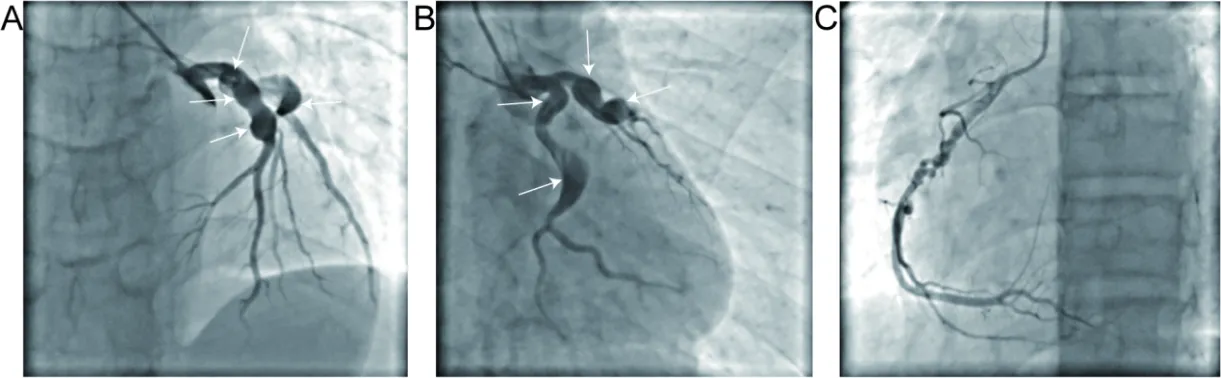

A 16-year-old boy with a medical history of KD presented to the cardiology clinic with occasional precordial discomfort for 3 months, following a recent hospital admission for acute inferior myocardial infarction (AIMI) on 15 July 2022. The patient’s “atypical KD” was first diagnosed in 2012 when he was 6 years old. Initially, the boy presented with persistent fever for more than 2 weeks, accompanied by cervical lymph node swelling and erythema multiforme. Echocardiography showed no obvious coronary ectasia at that time. Therefore, the boy was diagnosed as KD somewhat empirically. However, his parents couldn’t provide enough information about the specific drug regimen then, except for the nonacceptance of standard medication, including intravenous immunoglobulin (IVIG). According to his parents’ description, the boy has not experienced any acute recrudescence or accepted any specific therapy during the past 10 years. Given the low overall recognition of KD, this family ignored a close follow-up, including any cardiac imaging. Three months ago, the juvenile presented to the local emergency department at 6:06 a.m., complaining of a 2-h history of aggravating chest pain with sweating, shortness of breath, malaise and even an unconscious apopsychia for 5 min. Vital signs on arrival were unremarkable except for a severe decrease in blood pressure (BP) to 74/41 mmHg. Electrocardiogram (ECG) demonstrated an inferior-wall MI. Emergency CAG revealed a total obstruction in the middle of the left circumflex coronary artery (LCX) and ectasia at the proximal portion with TIMI 0 level. The left anterior descending artery (LAD) was also observed to have proximal ectasia and distal occlusion with TIMI 0 level. Severe tortuosity and ectasia existed in the middle of the right coronary artery (RCA), while maintaining a TIMI III level (Figure 1A,B). Thus, the diagnosis of CAAs was confirmed. Given diffuse ectatic changes of all coronaries with no suitable lesion identified for stenting, he was only managed with balloon angioplasty and intracoronary thrombolysis for LCX, the culprit vessel (Figure 1C). After the BP stabilized at a normal level, the patient was admitted to the Coronary Care Unit (CCU) for comprehensive medical treatment.Upon admission, laboratory findings revealed several abnormalities: the routine blood test exhibited a white blood cell (WBC) count at 12.2 × 109/L (normal range, 4 × 109–10 × 109/L), a neutrophil count at 8.5 × 109/L (normal range, 1.8 × 109–6.3 × 109/L) and a monocyte count at 1.23 × 109/L (normal range, 0.1 × 109–0.6 × 109/L). Additionally, cardiac biomarkers were also notable, with an elevated serum creatine kinase (CK) level of 2468.00 U/L (nomal range, 0–190 U/L), a creatine kinase isoenzyme level of 164.4 U/L (normal range, 0–24 U/L), a cardiac troponin I (cTnI) level of 1.48 ng/mL (normal range, ≤1.75 ng/mL) and an N-terminal pro-brain natriuretic peptide (NT-proBNP) level of 509.76 pg/mL (normal range, 0–125 pg/mL). Liver function tests indicated elevated serum aspartate aminotransferase (AST) at 288.6 U/L (normal range, 0–38 U/L), alanine aminotransferase (ALT) at 73.2 U/L (normal range, 0–38 U/L) and total bilirubin (TBIL) at 48.2 ummol/L (normal range, 2–20.4 ummol/L). Lipid panel showed a low-density lipoprotein cholesterol of 1.99 mmol/L (normal range, 0–3.36 mmol/L), high-density lipoprotein cholesterol of 1.01 mmol/L (normal range, 1.03–1.55 mmol/L) and that the total cholesterol and triglyceride were both within normal limits. The patient received medical treatment comprising anticoagulation with low-molecular-weight heparin (LMWH), dual antiplatelet therapy (DAPT) with aspirin and clopidogrel, a β-receptor blocker (betaloc), a lipid-lowering drug (atorvastatin), diuretics (furosemide and spironolactone) and a proton pump inhibitor (PPI) (pantoprazole). By the second hospital day, the serum cTnI level had decreased to 0.68 ng/mL. By the third day, the blood routine results had normalized, although mild hepatic insufficiency persisted. An echocardiography performed on July 20th revealed a left ventricular ejection fraction (LVEF) of 54% and segmental dyskinesia in the inferior posterior wall of the left ventricle. After 12 days of medical treatment, the patient’s general condition improved significantly, leading to his discharge from the local hospital.

Figure 1. Representative emergency CAG images during the AMI in April 2022. (<b>A</b>) Proximal large ectasia, total obstruction of LCX, and proximal large ectasia and distal occlusion of LAD. (<b>B</b>) Severe tortuosity and diffuse ectasia of RCA. (<b>C</b>) Still, nearly 80% remnant stenosis in the middle segment of LCX after balloon angioplasty and intracoronary thrombolysis.